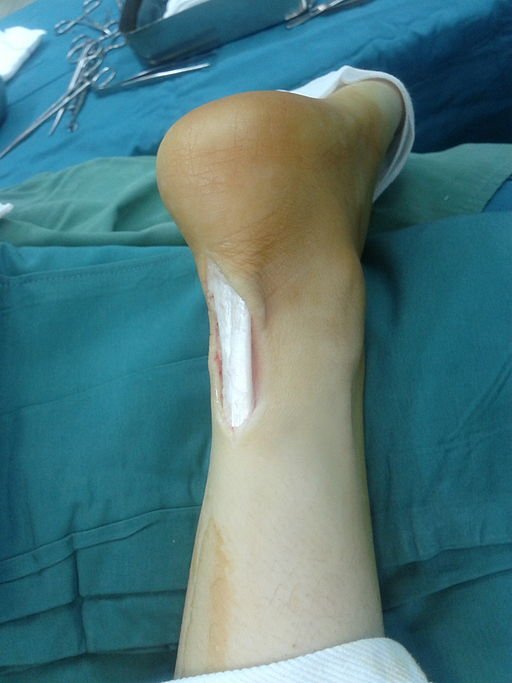

المرحلة الثالثة: التدخل الجراحي

يتم اللجوء للجراحة كخيار أخير في حالات الالتهاب المزمن التي لم تستجب لأي علاج آخر، أو في حالة وجود تمزقات جزئية كبيرة في الوتر. يشمل العلاج الجراحي لوتر اكيليس تنظيف الوتر وإزالة الأنسجة المتآكلة، أو حتى ترقيع الوتر إذا كان الضرر كبيراً.